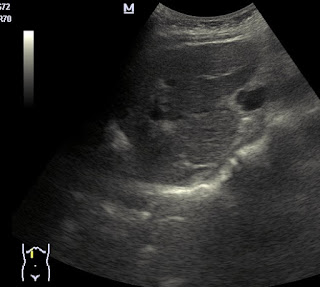

Quiste hidatídico hepático gigante y quiste renal izdo.

La primera imagen correspnde al hidatide de higado que ya es antiguo y está tratado e inactivo, las dos últimas corresponden al de riñon (espero que me lo confirmeis) que salio inesperadamente en la eco.

Un abrazo para todos.